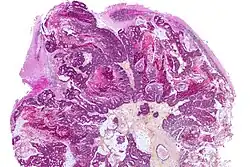

Resected fragments of a brain tumor, and in this case the very dark appearance supports a diagnosis of metastatic pigment-forming melanoma